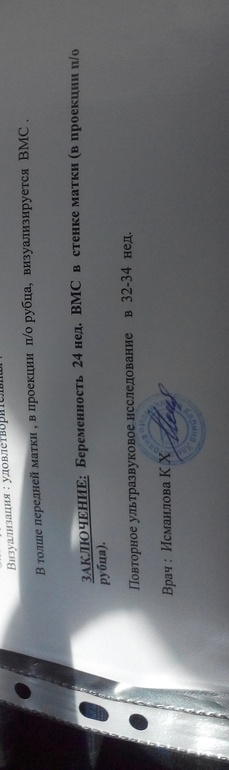

Я забеременела после Удаления второй спирали ))). Первая была не в полости матки , удалили ее во время планового кс . Пепфорировала в рубец.

Об извлечении речи нет(((. Я после каждого ребенка ставила -все хорошо было. А после кесарева вот такая опа случилась(((

очень надеюсь )) если б просто спираль , а тож она в рубец засела (